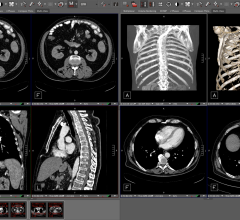

Radiology departments have many different needs and face a wide variety of challenges that can impact their departments ...

Bayer Radiology’s Barbara Ruhland and Thom Kinst discuss how radiology departments can address the many different ...